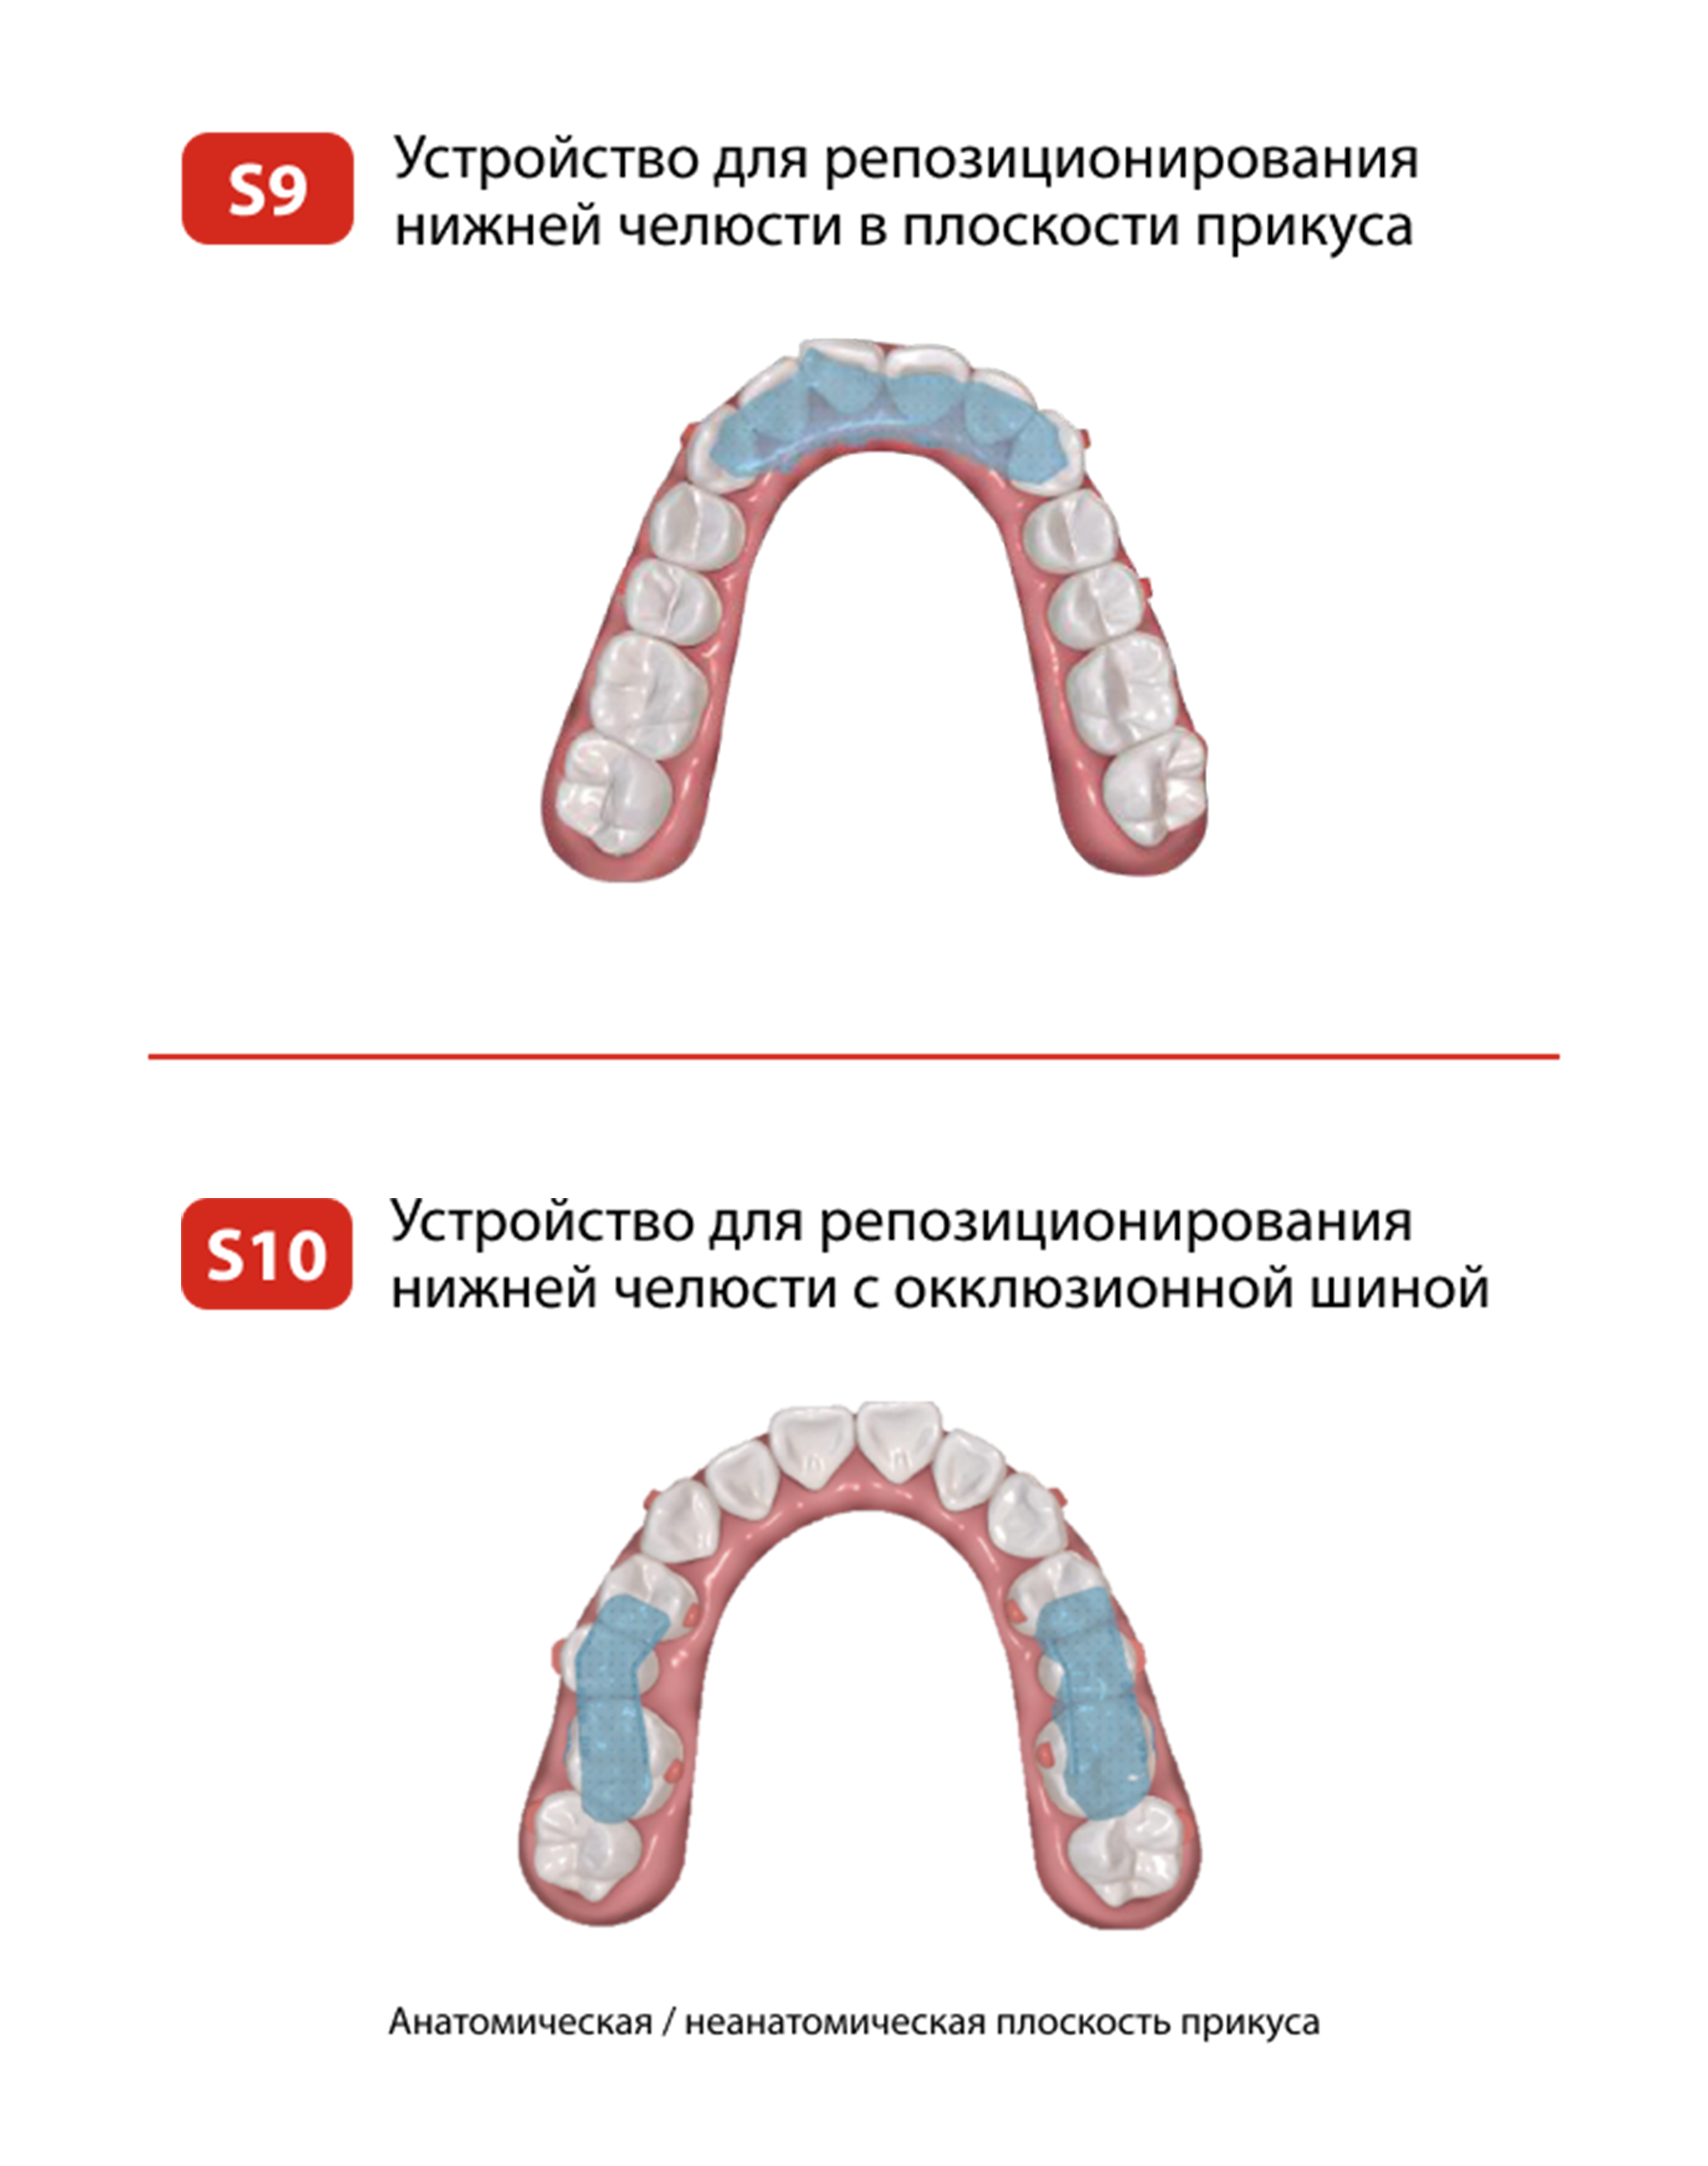

Программное обеспечение

Smartee технологии

Smartee технологии

SMARTEE ТЕХНОЛОГИИ

Продуктовая линейка

ПРОДУКТОВАЯ ЛИНЕЙКА